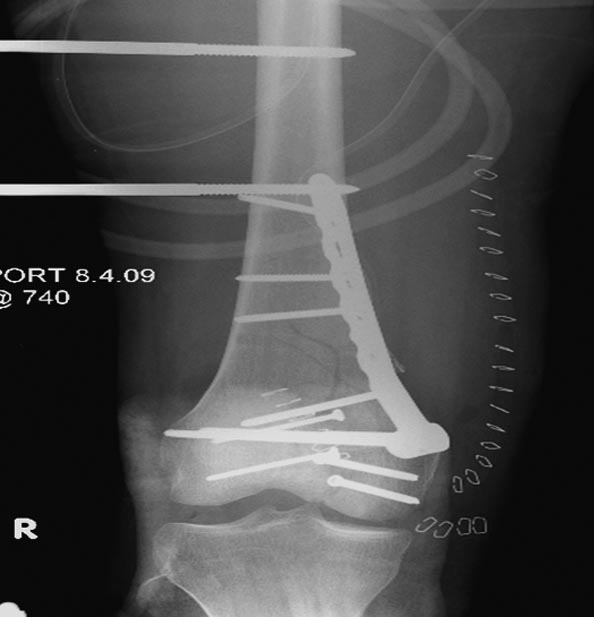

Раны в области коленного сустава и на плече до сих пор чистые, остаются открытыми. Отсутствует признаки инфекции, решили превратить недостаток в преимущество, т.е. фиксировать через открытые раны пластинами.

На 9й день фиксация дистального бедра, где фрагмент Hoffa и вертикальный перелом надколенника, зафиксированы винтами.

На 11й день фиксация плеча также пластиной.

На 25 день с момента травмы операция на Jackson table с боковым обширным доступом. Удаление стержней с местной обработкой. В тазобедренном суставе удаление головки, на дне вертлужной впадины полная отслойка хряща. Вертлужный компонент с одним винтом и короткая ножка - Fitmore press fit stem. На второй день однократно доза радиации для профилактики гетеретопической оссификации. Послеоперационный период без температуры. Выписана. Нагрузку разрешили на левой стороне, а полная в 3 мес. Здесь снимки при амбулаторном наблюдении: послеоперационно, 2 мес, 3 мес и 6 мес. Нагрузка полная, отсутствует хромота, и нет жалоб.